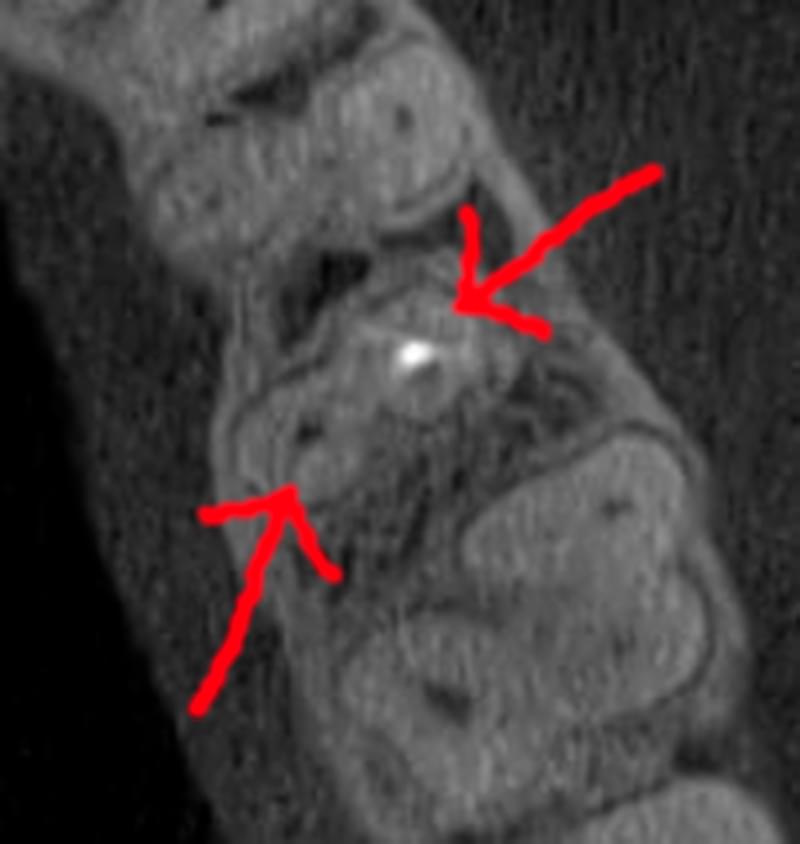

Зуб — це не просто монолітний об'єкт, а складна система мікроканалів. На плоскому 2D-знімку вони часто перекривають один одного, створюючи ілюзію простої анатомії.

Непомічений канал — це джерело майбутньої інфекції та причина «загадкового» болю після лікування. Завдяки високій роздільній здатності обладнання MyRay, лікар бачить кожен мікронний канал ще до того, як візьме до рук інструмент.

Коли коріння «ховає сюрпризи» - Корені зубів часто мають складну кривизну, гачкоподібні закручення або розгалуження, які на звичайному 2D-знімку накладаються один на одного, створюючи ілюзію прямого каналу. На плоскій картинці неможливо побачити реальний об'єм та напрямок вигину, що критично важливо при видаленні «зубів мудрості» або ендодонтичному лікуванні. КТ MyRay дає змогу лікарю заздалегідь побачити 3D-геометрію кожного кореня, оцінити його близькість до нижньощелепного нерва чи гайморової пазухи та підібрати правильну тактику роботи. Це мінімізує ризики поломки інструменту в каналі або травмування сусідніх структур, перетворюючи складну хірургію на прогнозовану процедуру.